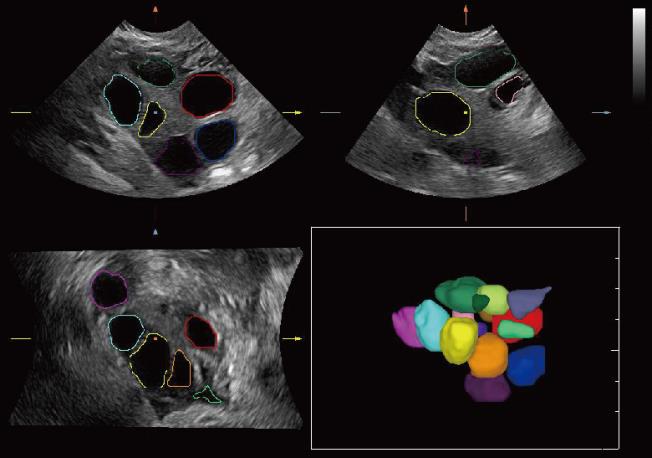

Smart Planes

Благодаря уникальной новаторской технологии компании Mindray, система Resona 6 является новейшей системой ультразвуковых исследований, обеспечивающей полностью автоматическое и точное получение особо важных проекций и проведение наиболее часто используемых измерений ЦНС плода, что обусловливает интеллектуальную диагностику, улучшение производительности и снижение зависимости от пользователя.

Smart Planes — это удобный для пользователя инструмент, значительно повышающий эффективность сканирования за счет увеличения точности в сочетании с автоматизацией работы. Одного нажатия на клавишу достаточно, чтобы из 3D данных, полученных при сканировании мозга плода, немедленно получить стандартные плоскости сканирования ЦНС: MSP (медиальная сагиттальная плоскость), TCP (трансцеребральная плоскость), TTP (трансталамическая плоскость) и TVP (трансвентрикулярная плоскость), а также получаемые в них измерения (БПР, ОГ, ЛЗР, Поперечный Диаметр Мозжечка, Большая Цистерна и Ширина Бокового Желудочка).

• 06 Smart Planes